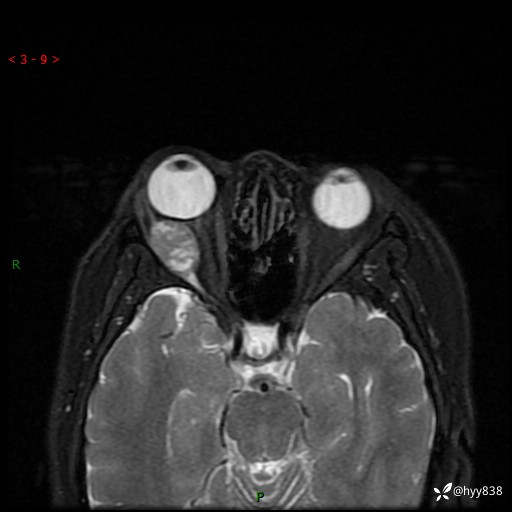

老年女性,右眼球突出1月。说说鉴别诊断,看谁第一个秒---(有结果)

主诉:发现右眼球突出1月余

简要病史:患者于1月前无明显诱因发现右眼球突出,偶感磨痛、眼胀,无视力下降,无头痛,恶心呕吐等不适。10天前就诊于当地县人民医院就诊,完善头颅ct检查,诊断为右侧眼眶肿物,建议患者上级医院进一步治疗,患者因个人原因拒绝。拟行手术,来我院就诊,门诊行相关检查后以“右眼眼眶肿物”收入院。 患病以来,患者精神饮食睡眠尚可,大小便如常、体重无明显改变。

辅助检查:MRI

临床诊断:眼眶肿物

眼眶MRI平扫+增强